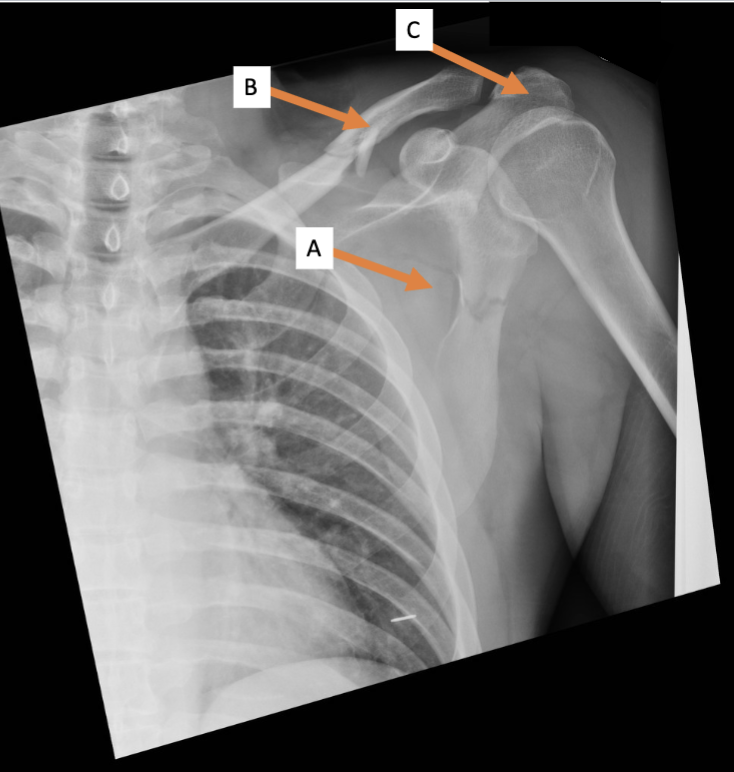

A. Identify structure

Transverse foramen; Vertebral a.

B. Identify structure; What goes through this feature?

Transverse process

C. Identify structure

Scapula

A. Identify the bone

Clavicle

B. Identify the bone

Acromion process

C. Identify the structure